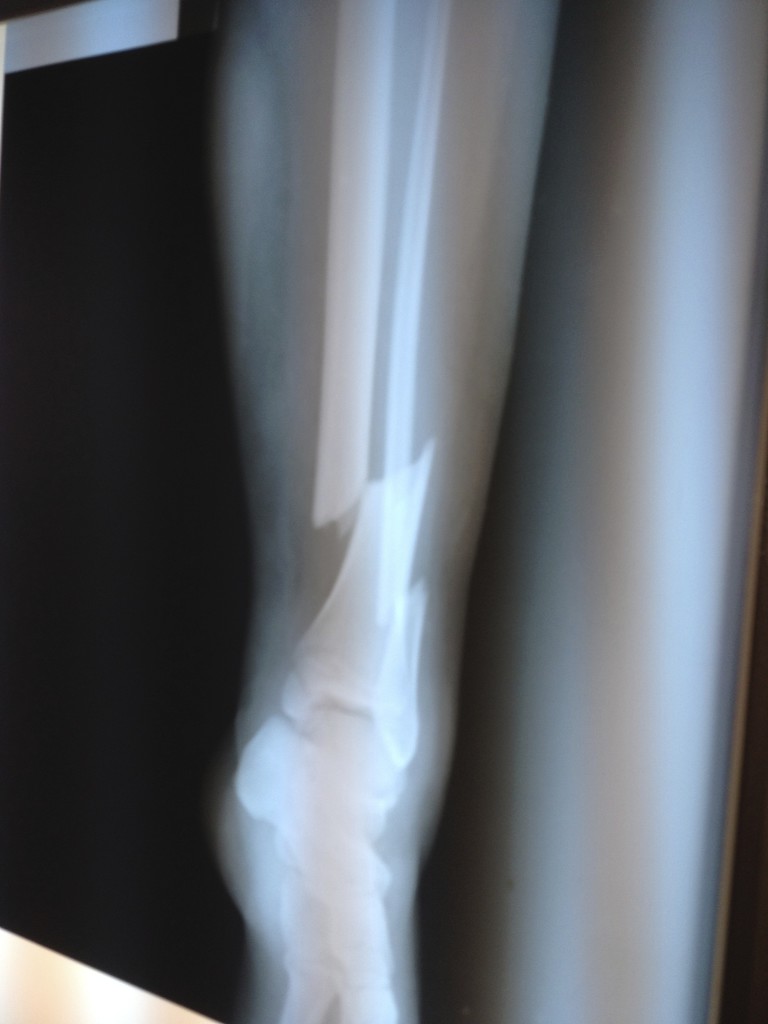

My life had just turned 180 degrees around suddenly. As expected, the personnel on this tiny clinical center didn't have much sources to attend the case, so they just applied a cast and did some X-Rays to see which type of fracture I had. My dad managed to get a helicopter to get me back to the city as fast as they could. As soon as I got there, we went to a very good local hospital and I was attended by who would be my orthopedist for the next 2 weeks. My leg was so swollen by the impact they had to wait for it to drain totally and then start doing surgery. Those 2 weeks passed by as I got 4 or 5 surgeries and other rides to the surgery room for draining processes.

My mom had been telling me about the plan of going to the US and to verify if everything that had been done was right. We researched everything about the HSS, how it was ranked number 1 in Orthopedics and had the best people to treat me. Dr. Austin Fragomen was the one who had to treat my case. As soon as I went to the hospital, the kindness of everyone lessens the fright you feel being a teenager, away from everything you had before. I can definitely say you'll always be in the safest (underlined) hands as soon as you contact the hospital. I have to admit, when I got to the appointment and all I heard was "this has to be done again", I knew it was going to be a long ride. Words of relief were told to me by the PA: "we always win." And so they do. 1 month at the hospital, I had been removed the previous external fixator and had been applied frames to hold my bones together. I got a bone graft, a skin graft (part of my skin was damaged as a consequence of the swelling), tibia and ankle surgery. I thank God everyday for teaching me so much at such a young age, and for putting me in the hands of the best people in the world that could manage this tragic case, being so many miles away. I will never be able to thank enough Dr. Fragomen for what he did, he saved my leg.